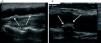

Carotid artery ultrasound, which measures cIMT and detects atheromatous plaques (Figure 1 A and Figure 1 B), is a strong indicator of overall vascular health. cIMT is a well recognized and accepted marker to predict cardiovascular disease.10

Carotid ultrasound is also the only available technique to localise the site of calcium deposition within the arterial wall. Our group has completed an ultrasound study examining the location of calcium in carotid and femoral artery wall..The brachial artery served as a negative control since this area is free of atherosclerosis.29 We observed that calcification was localized exclusively in the intimal layer, following two distinct patterns: 1) Calcification of the atheromatous plaque (Figure 2 A) and 2) Linear calcification of the intimal layer, anatomically unrelated to the atheromatous plaque (Figure 2 B). Multivariate analysis associated this previously unrecognized intimal calcium location with age, serum levels of phosphate and C-reactive protein, and with the presence of atheromatosis. These results underscore the contribution of inflammation and atheromatosis to the calcification of elastic arteries. Although serum phosphate levels remain a not fully resolved issue, we must start focussing on preventing atheromatosis and decreasing the pro-inflammatory status of CKD patients as much as possible.

Figure 1. Ultrasound image of carotid arteries

Figure 2. Calcification patterns depicted by ultrasound